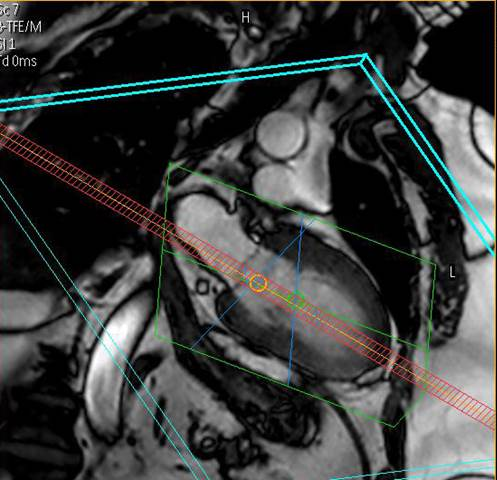

Das Deutsche Herzzentrum Berlin

spielt seit der Erstinstallation eines MR-Tomographen im Jahr 1996 eine weltweit führende Rolle bei der klinischen Anwendung, Forschung und Ausbildung auf dem Gebiet der CMR. Wir untersuchen mit zwei MRT-Systemen

modernster Bauart pro Jahr ca. 3000 Patienten, wobei das gesamte diagnostische Spektrum abgedeckt wird.

Equipment

Wir bieten modernste MRT-Diagnostik.

Ganzkörper MR System - Philips healthcare